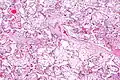

| Micrograph of villous immaturity. H&E stain. | |

Immature chorionic villi are larger and have more central blood vessels; thus, the diffusion distance for gas and nutrient exchange is larger and, therefore, placental function is impaired.

High mag.